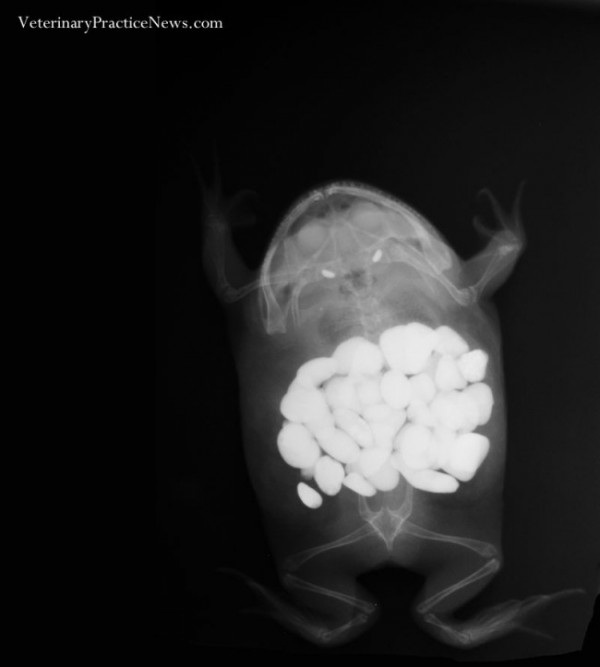

Лягушка съела 30 камешков

Как она вообще передвигалась?